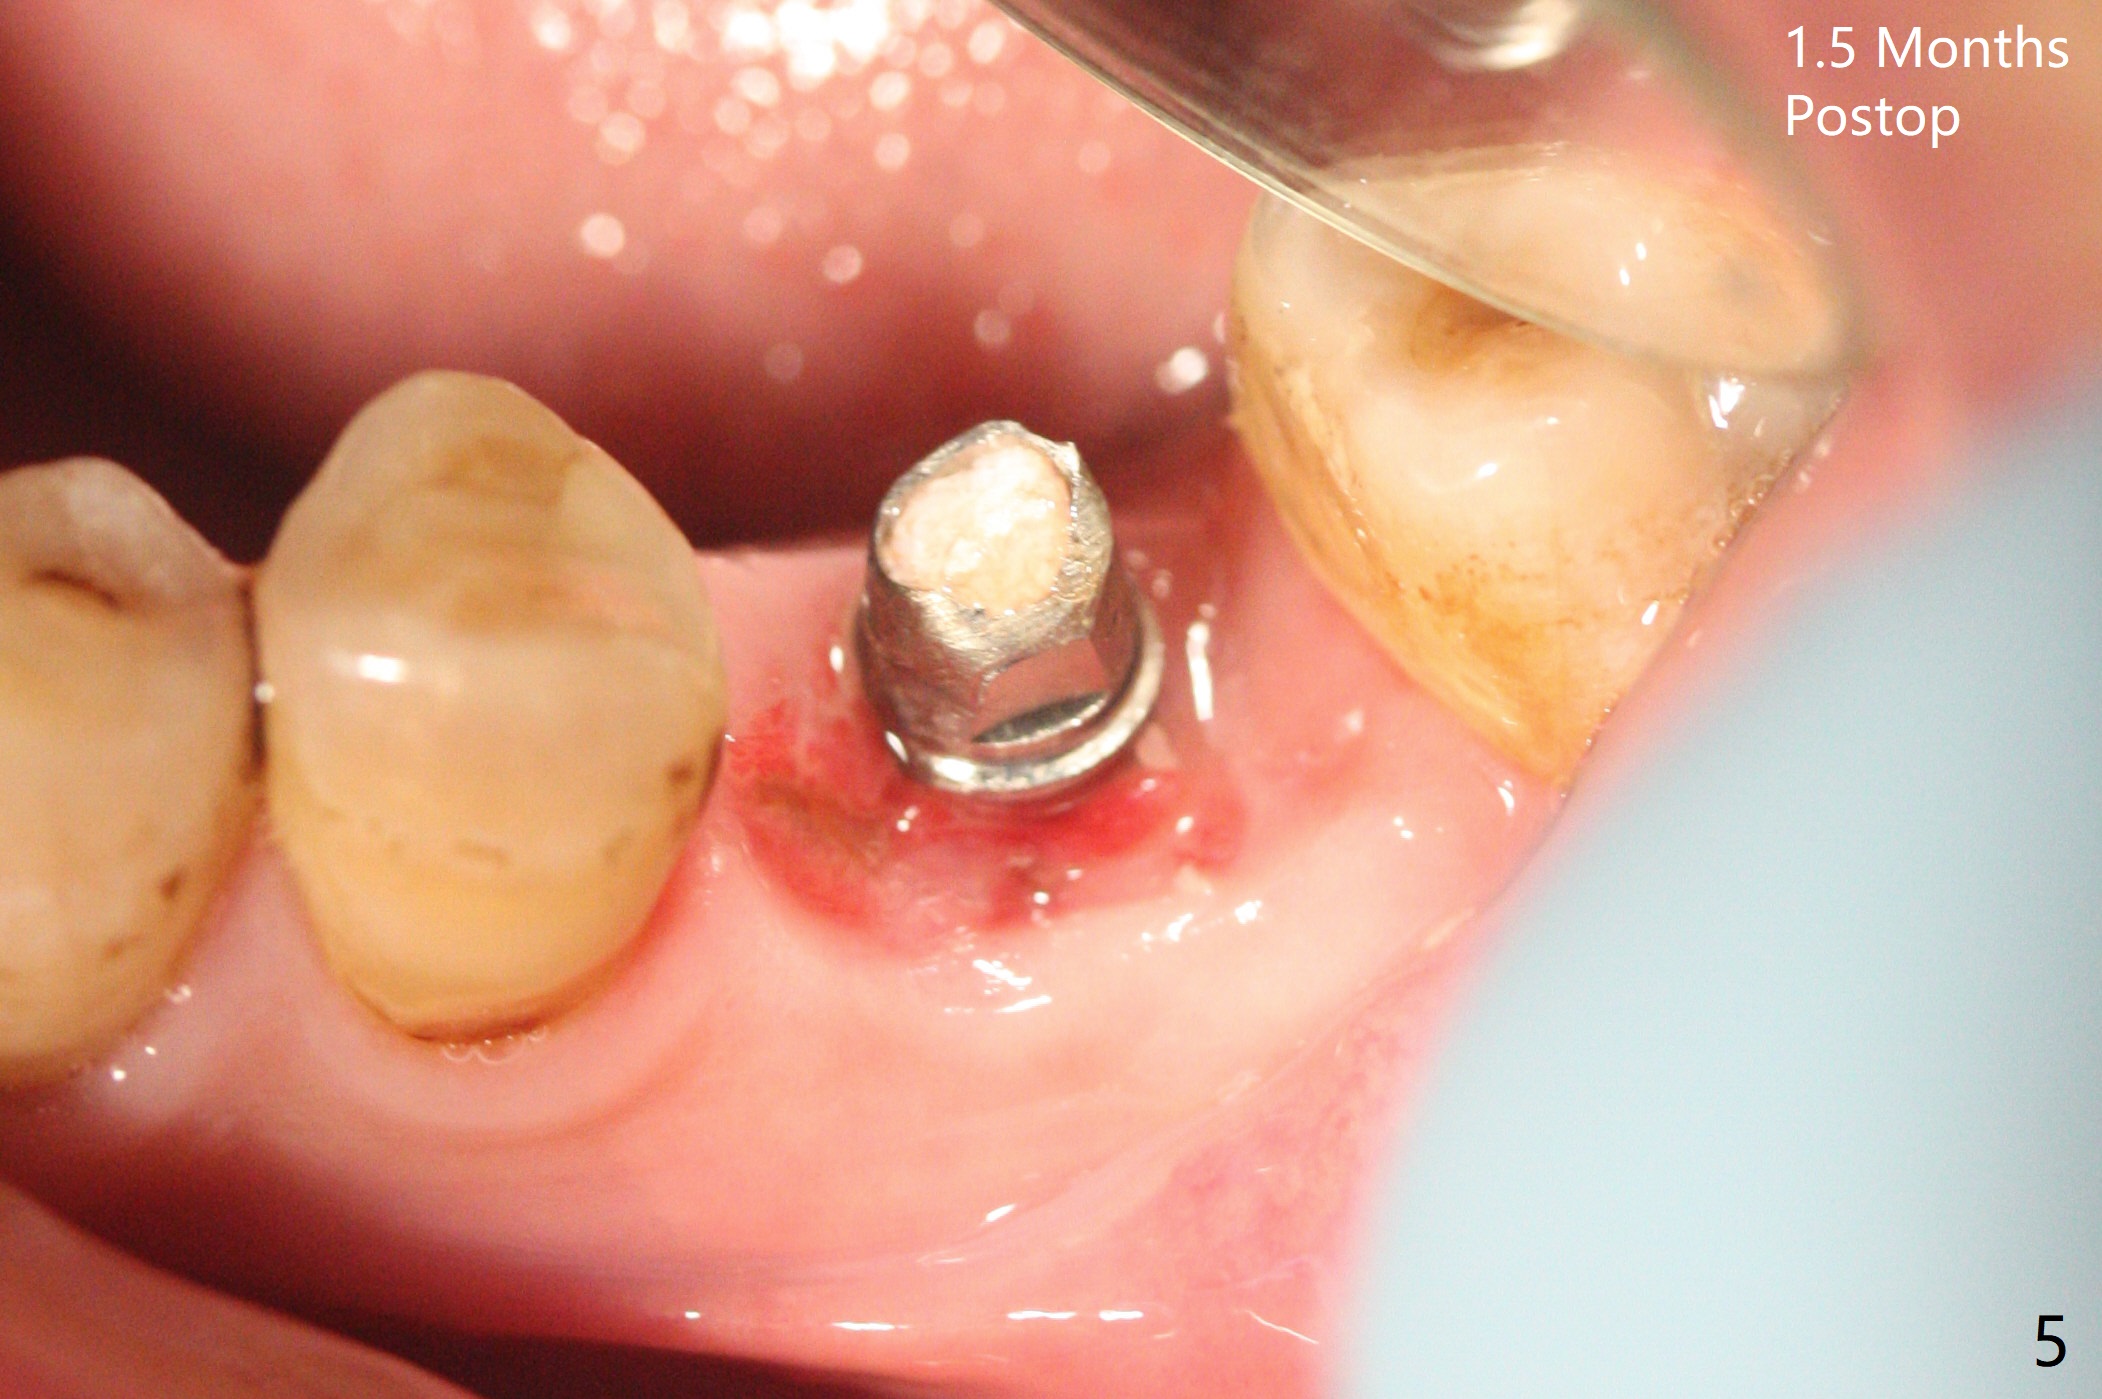

54岁男左下6根管治疗不成功,远中舌侧根弯曲,拔除时牙齿牙根多次断裂,骨质也硬,即使使用2.2毫米钻头也很吃力,钻至11.5毫米深,拍摄根尖片,显示钻洞没有明显偏移(图一),临床观察一致。当钻头直径增大,浅部钻洞,震动大,深部时,震动慢慢减少。为了植入5x11毫米植体,钻头必须4.5毫米,植体还必须反复倒旋转,才能减少扭力至40Ncm。由于没有骨质阻挡,基台放置尚顺利(图二)。拔牙时舌侧远中骨壁破坏,植入粘性骨粉重点放入 (图三:*),表面覆盖一张PRF膜(图四),最后制作临时牙冠。术后1.5月调整临时牙冠,牙槽窝愈合正常(图五)。